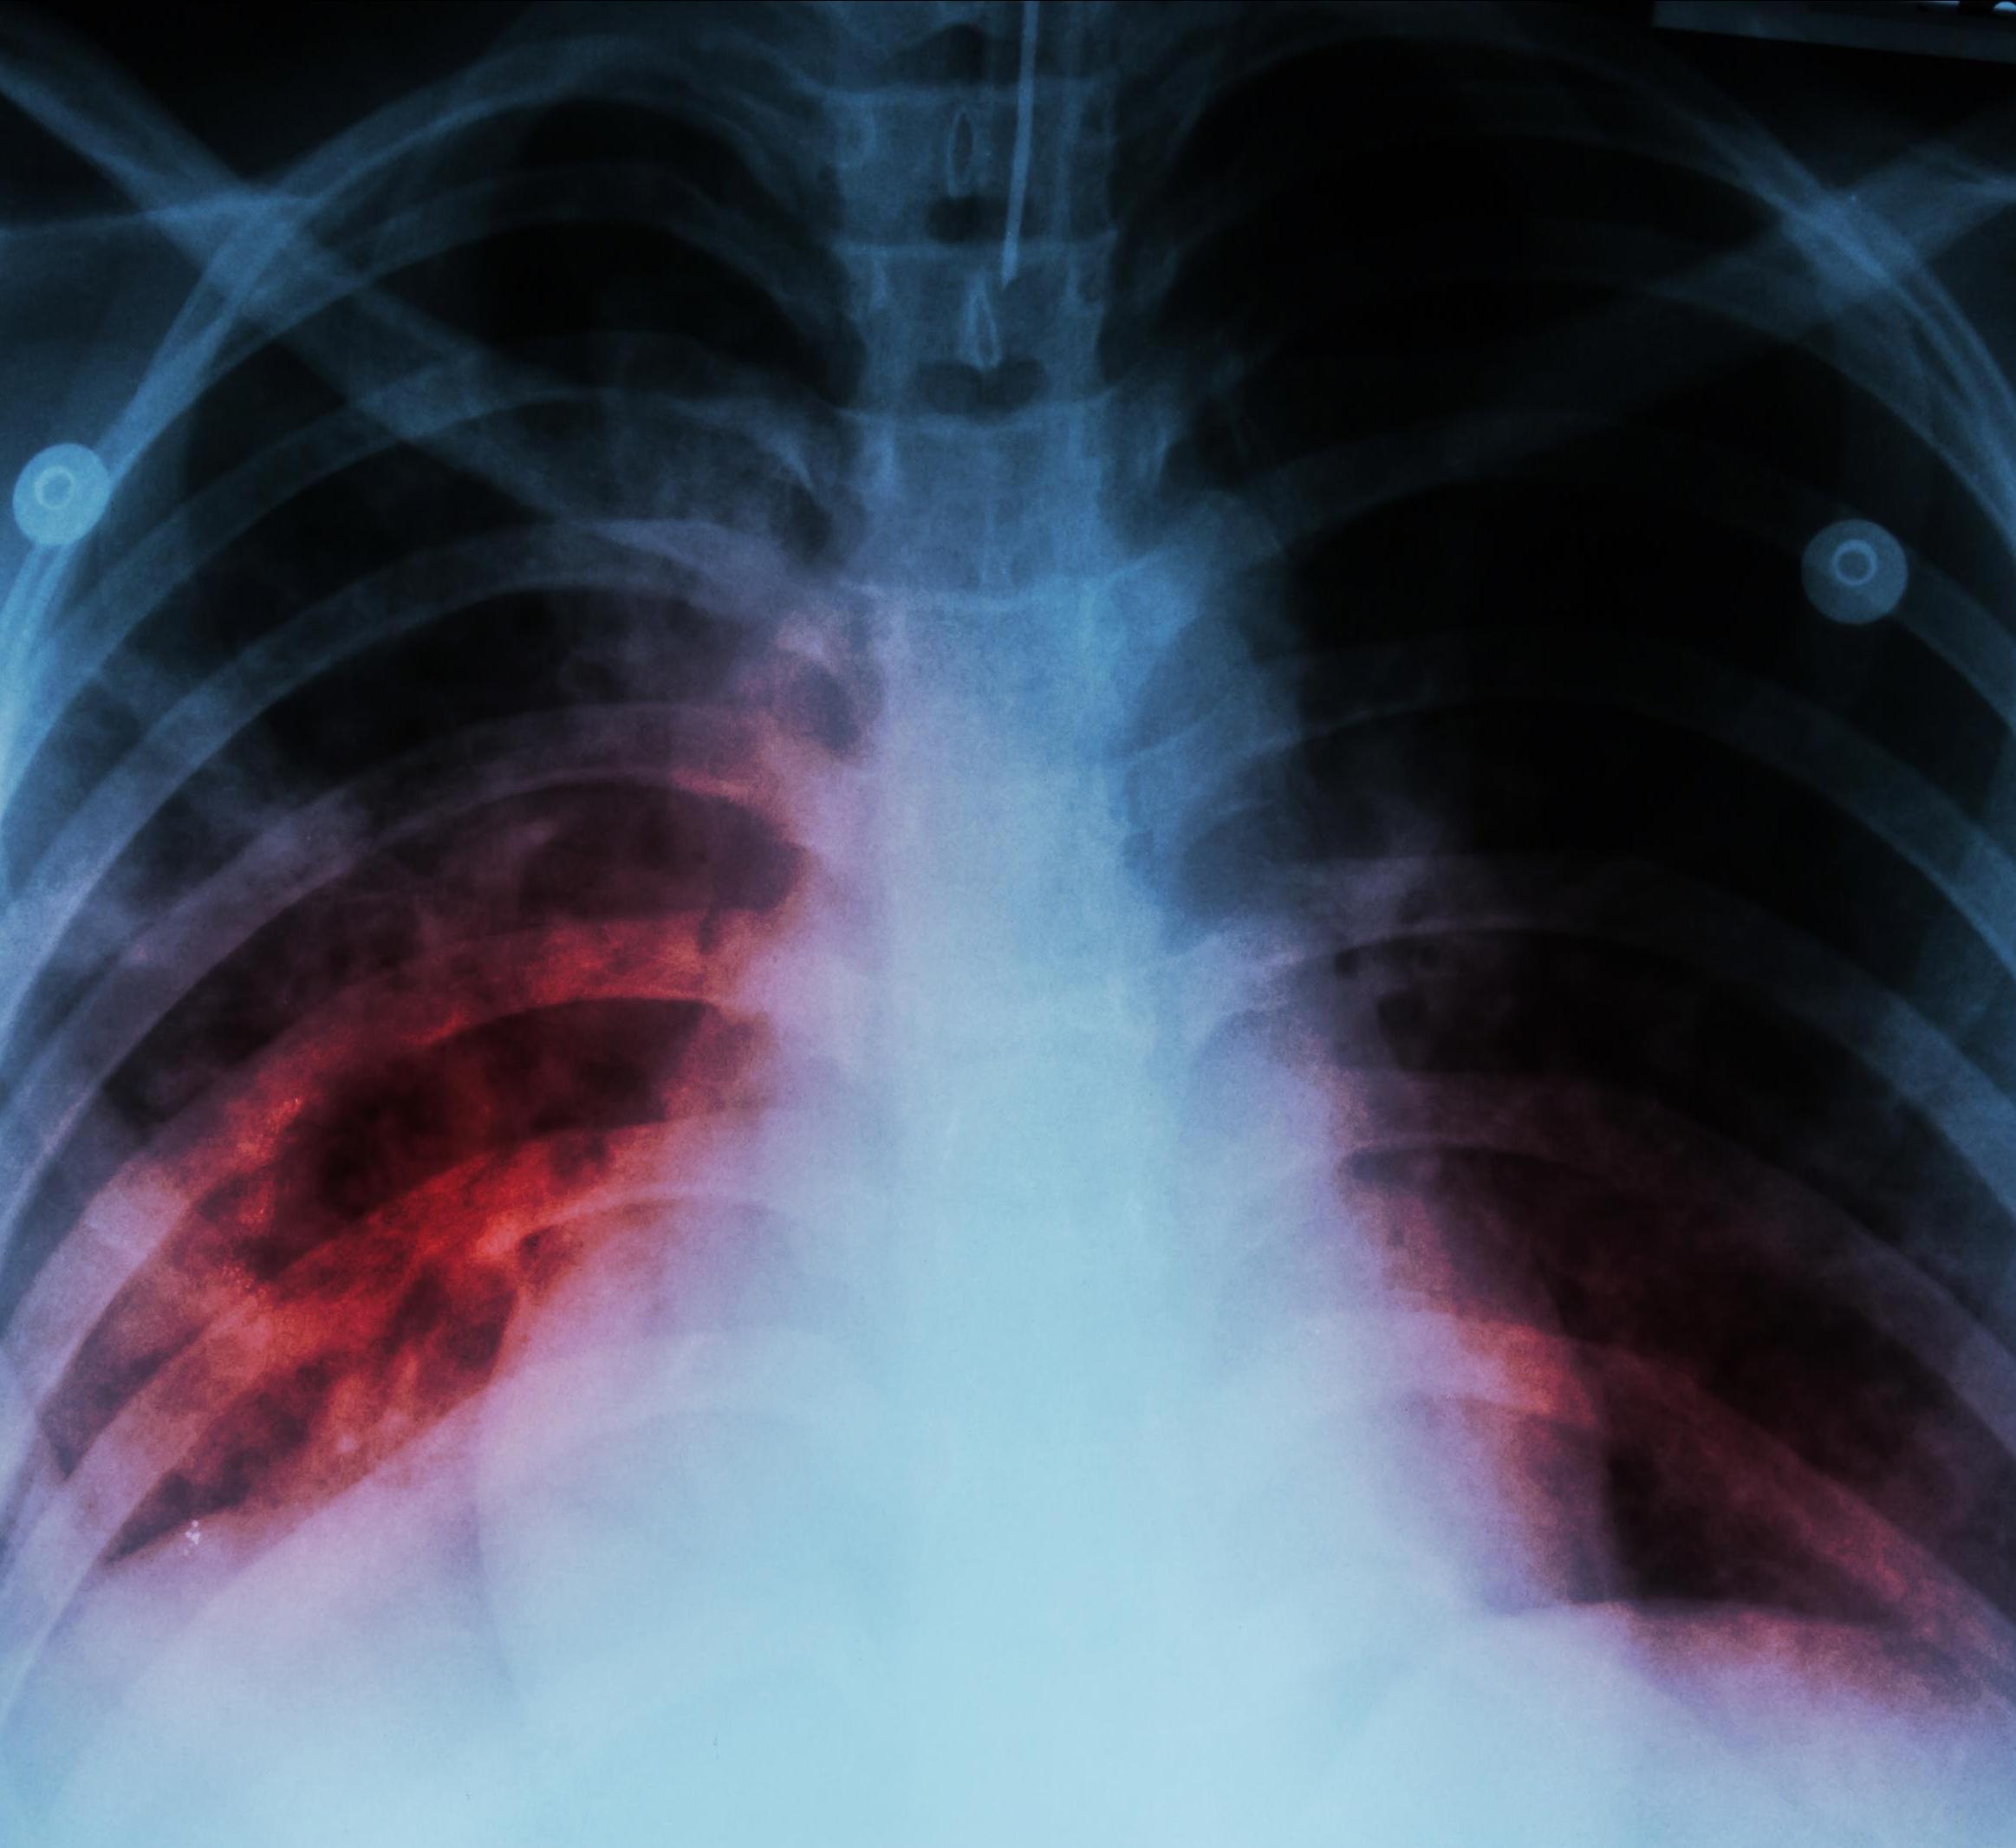

Even after successful tuberculosis treatment, patients have a "metabolic scar" that can be ameliorated with better nutrition.